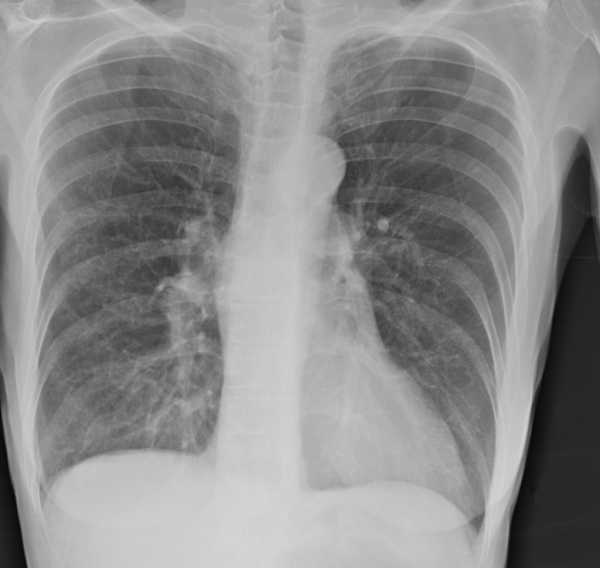

Среди симптомов эмфиземы следует отметить снижение веса, сутулость, выпячивание ямочек, которые находятся над ключицами, проблемы с прослушиванием дыхания, бочкообразную форму груди, сильную одышку. Если речь идет о развитии диффузной эмфиземы легких у взрослых (лечение ее довольно сложное), то на рентгене можно заметить, что диафрагма расположена слишком низко, а зона легких чересчур прозрачная. Сердце меняет свое положение, оно становится более вертикальным, а также возникает сильная дыхательная недостаточность. Симптоматика локализованной эмфиземы связано с тем, что травмированные участки легких давят на здоровые, поэтому у человека могут возникать даже приступы удушья.

Проводится сбор жалоб, анамнеза заболевания и анамнеза жизни пациента. Выполняется общий осмотр, прослушивание легких, общий анализ крови, рентгенография органов грудной клетки как один из ключевых методов диагностирования патологических изменений в легких. Проводится также компьютерная томография органов грудной клетки, спирометрия, исследование газового состава крови. Необходима консультация пульмонолога.

Рентген легких имеет большое значение при диагностике заболевания. У пациента с эмфиземой он покажет расширенные полости в различных отделах легких.